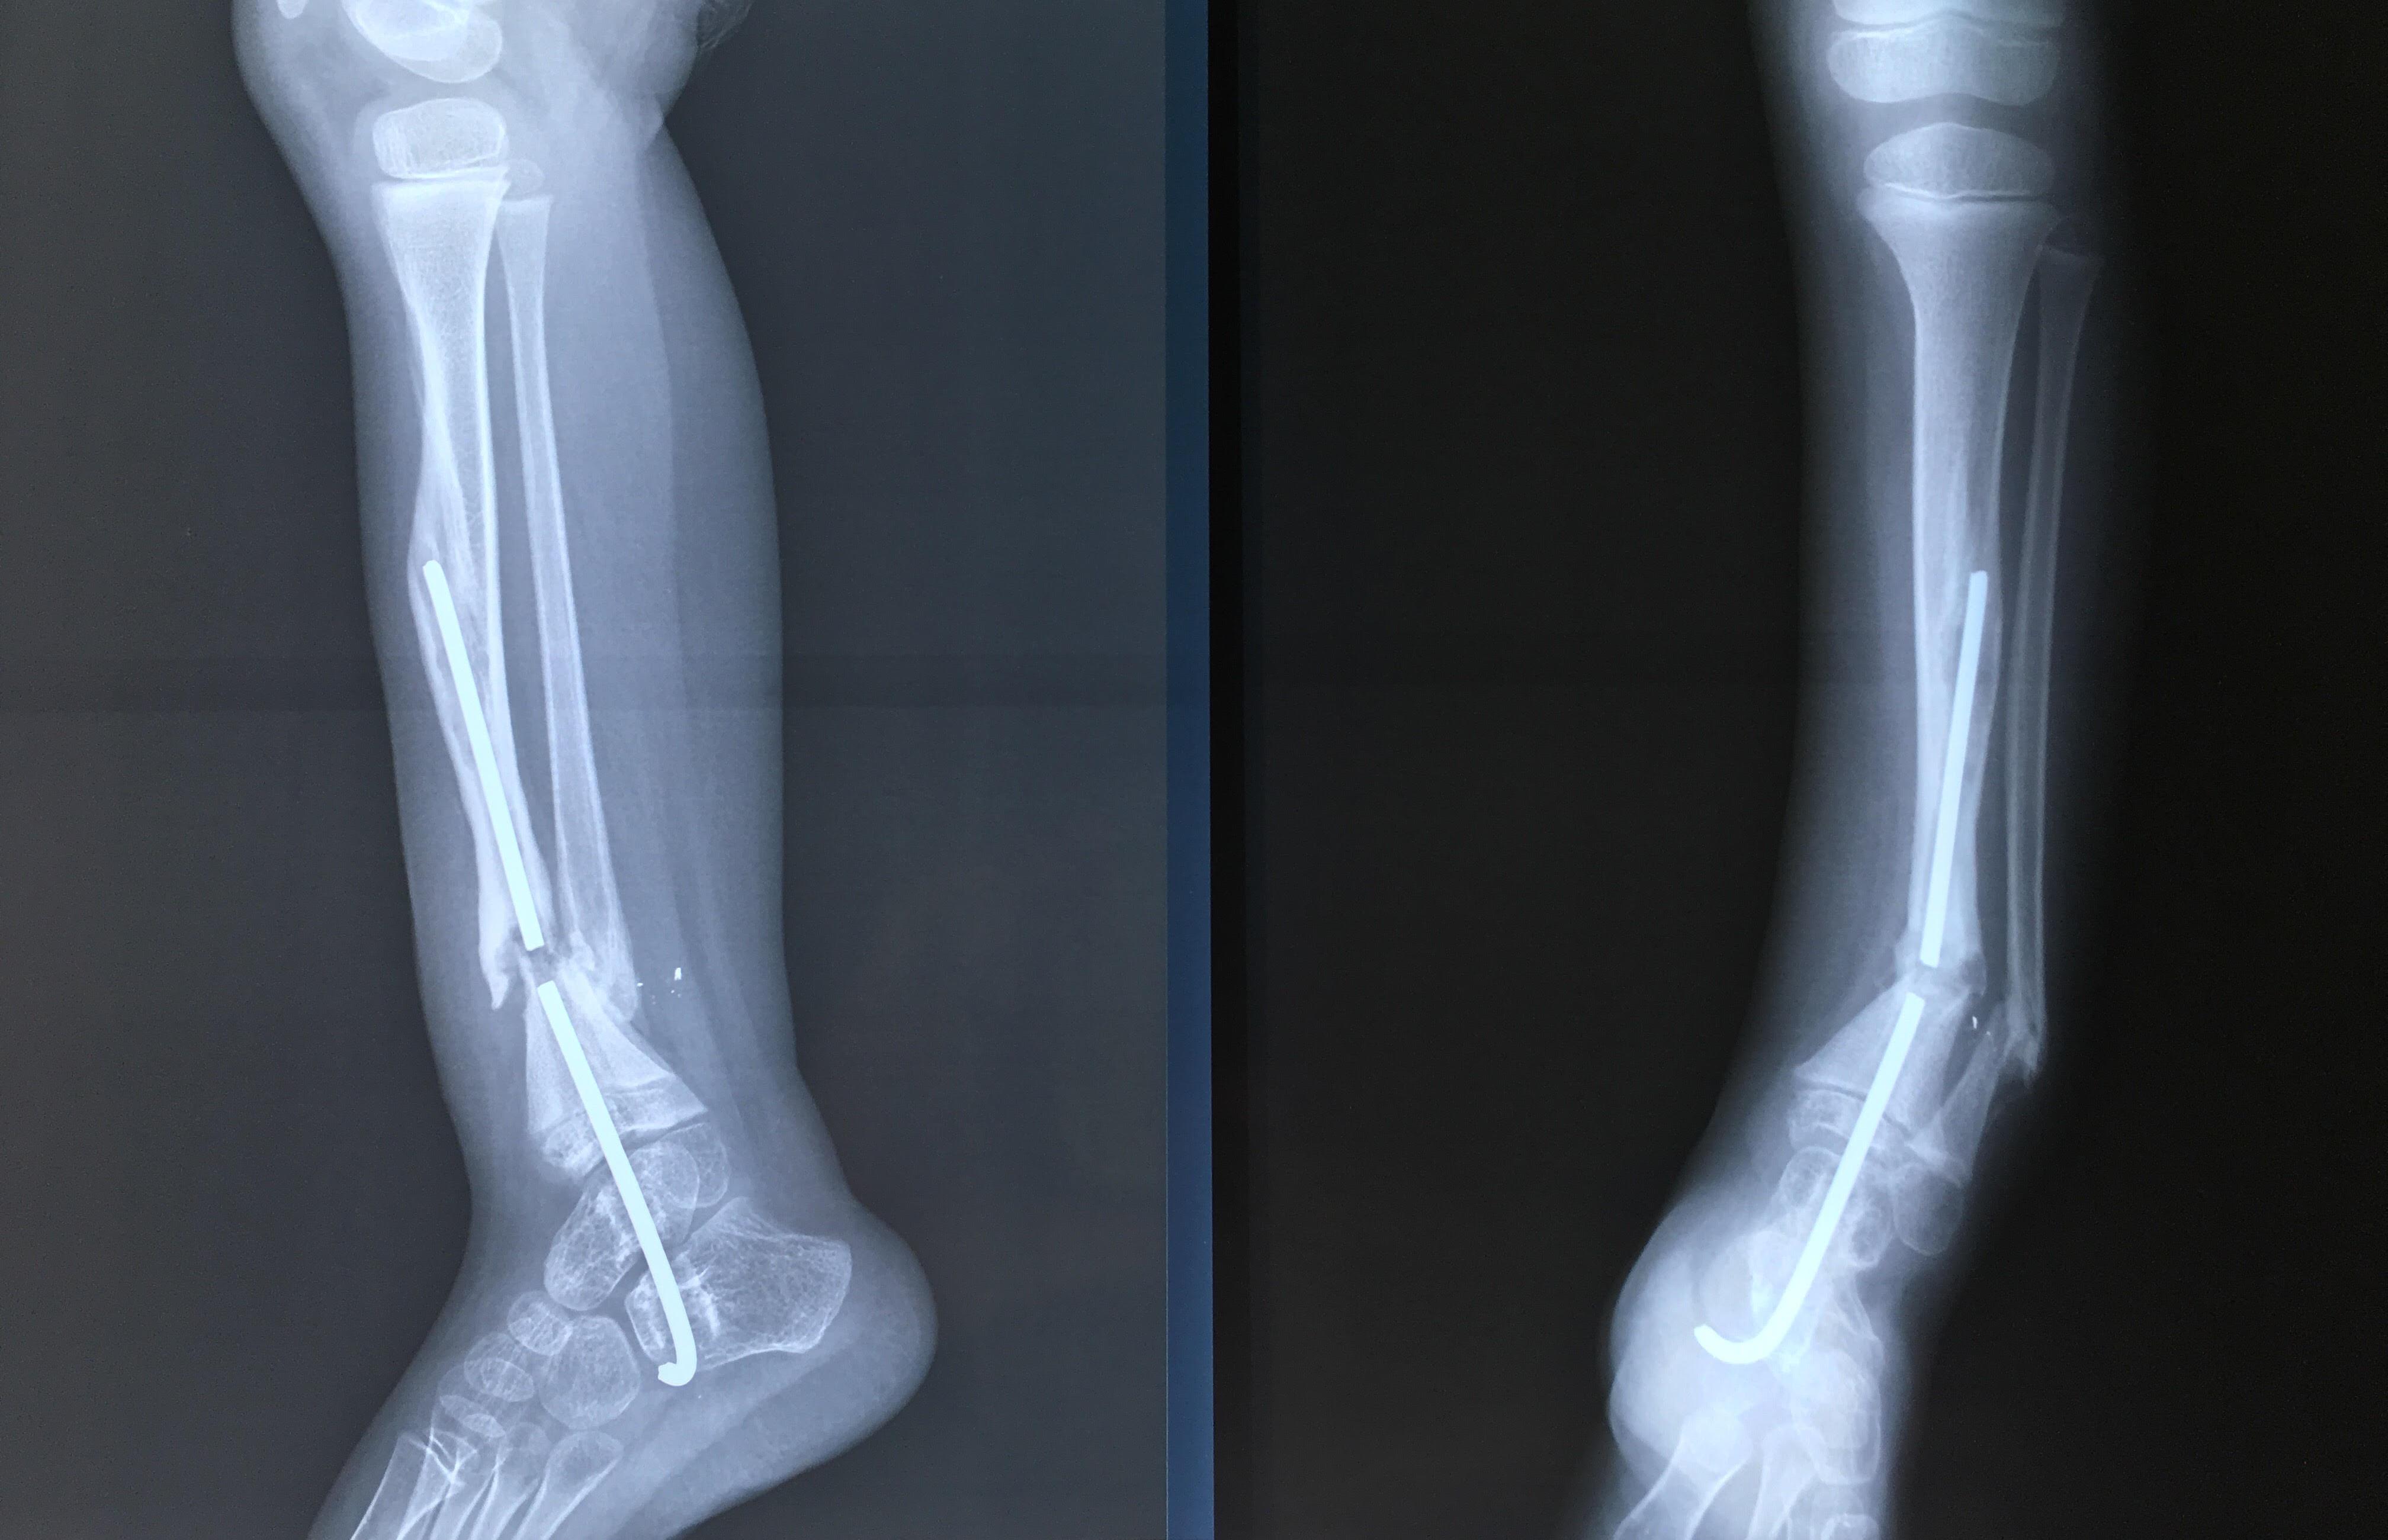

Phẫu thuật thành công ca bệnh hiếm gặp...khớp giả bẩm sinh xương chày

26/06/2019 17:00

Đã xem: 3137

Bệnh viện Chấn thương- Chỉnh hình Nghệ An, vừa phẫu thuật thành công cho bệnh nhi khớp giả bẩm sinh xương chày